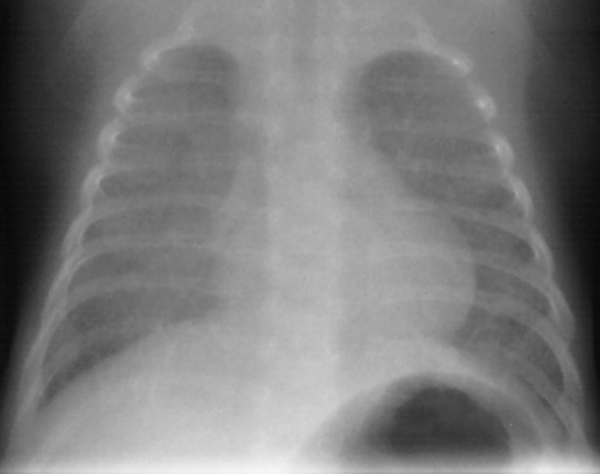

X线胸片

广泛肺不张(diffuse bilateral atelectasis)

透亮度减低,毛玻璃(groun-glass appearance)

颗粒网状阴影(granular-reticular appearance)

支气管充气征(air bronchograms)

groun-glass,granular-reticular appearance

No air bronchograms

Grade II-III RDS